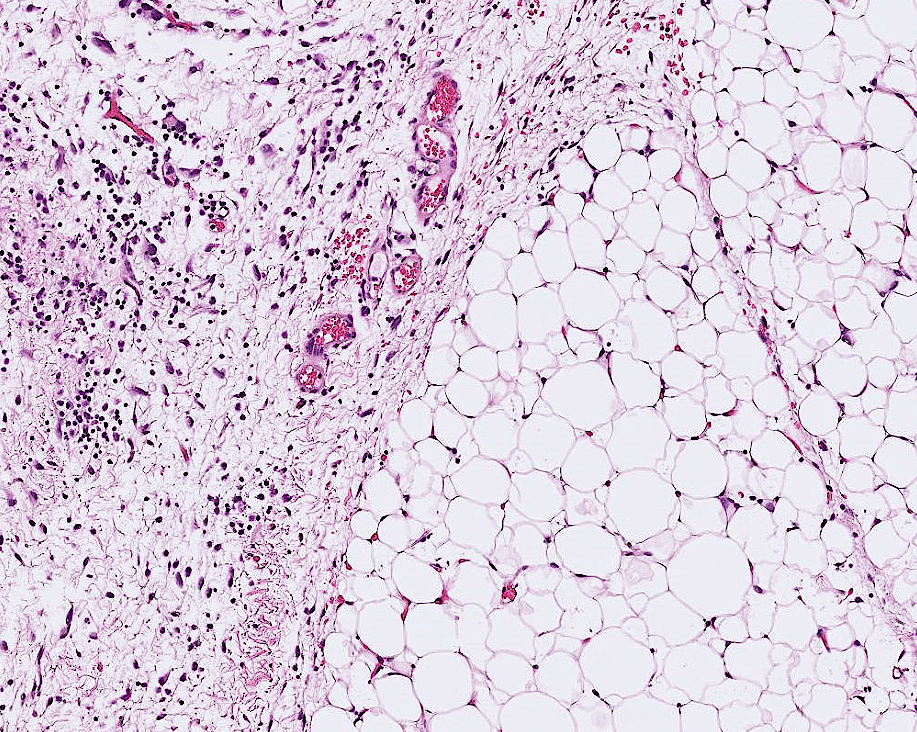

lung adenocarcinoma

colon cancer

endometrial cancer